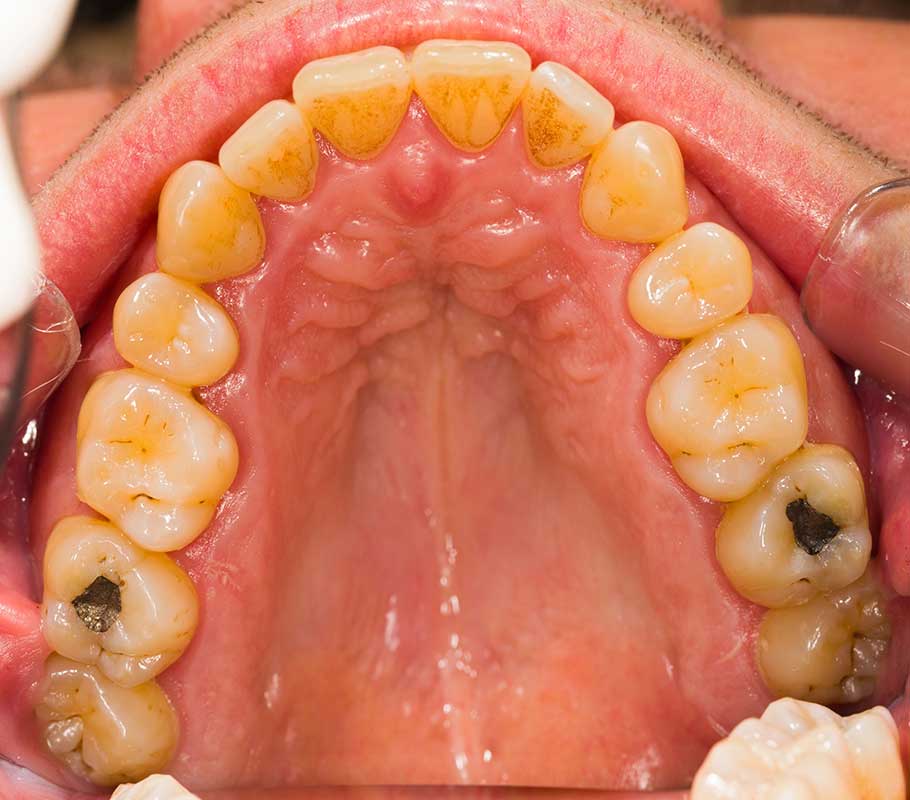

How do I know if I need a cavity filling?

Common signs that you need a cavity filling include tooth sensitivity, pain when chewing, or visible dark spots on your teeth. However, cavities don’t always cause symptoms — regular dental exams help catch them early.